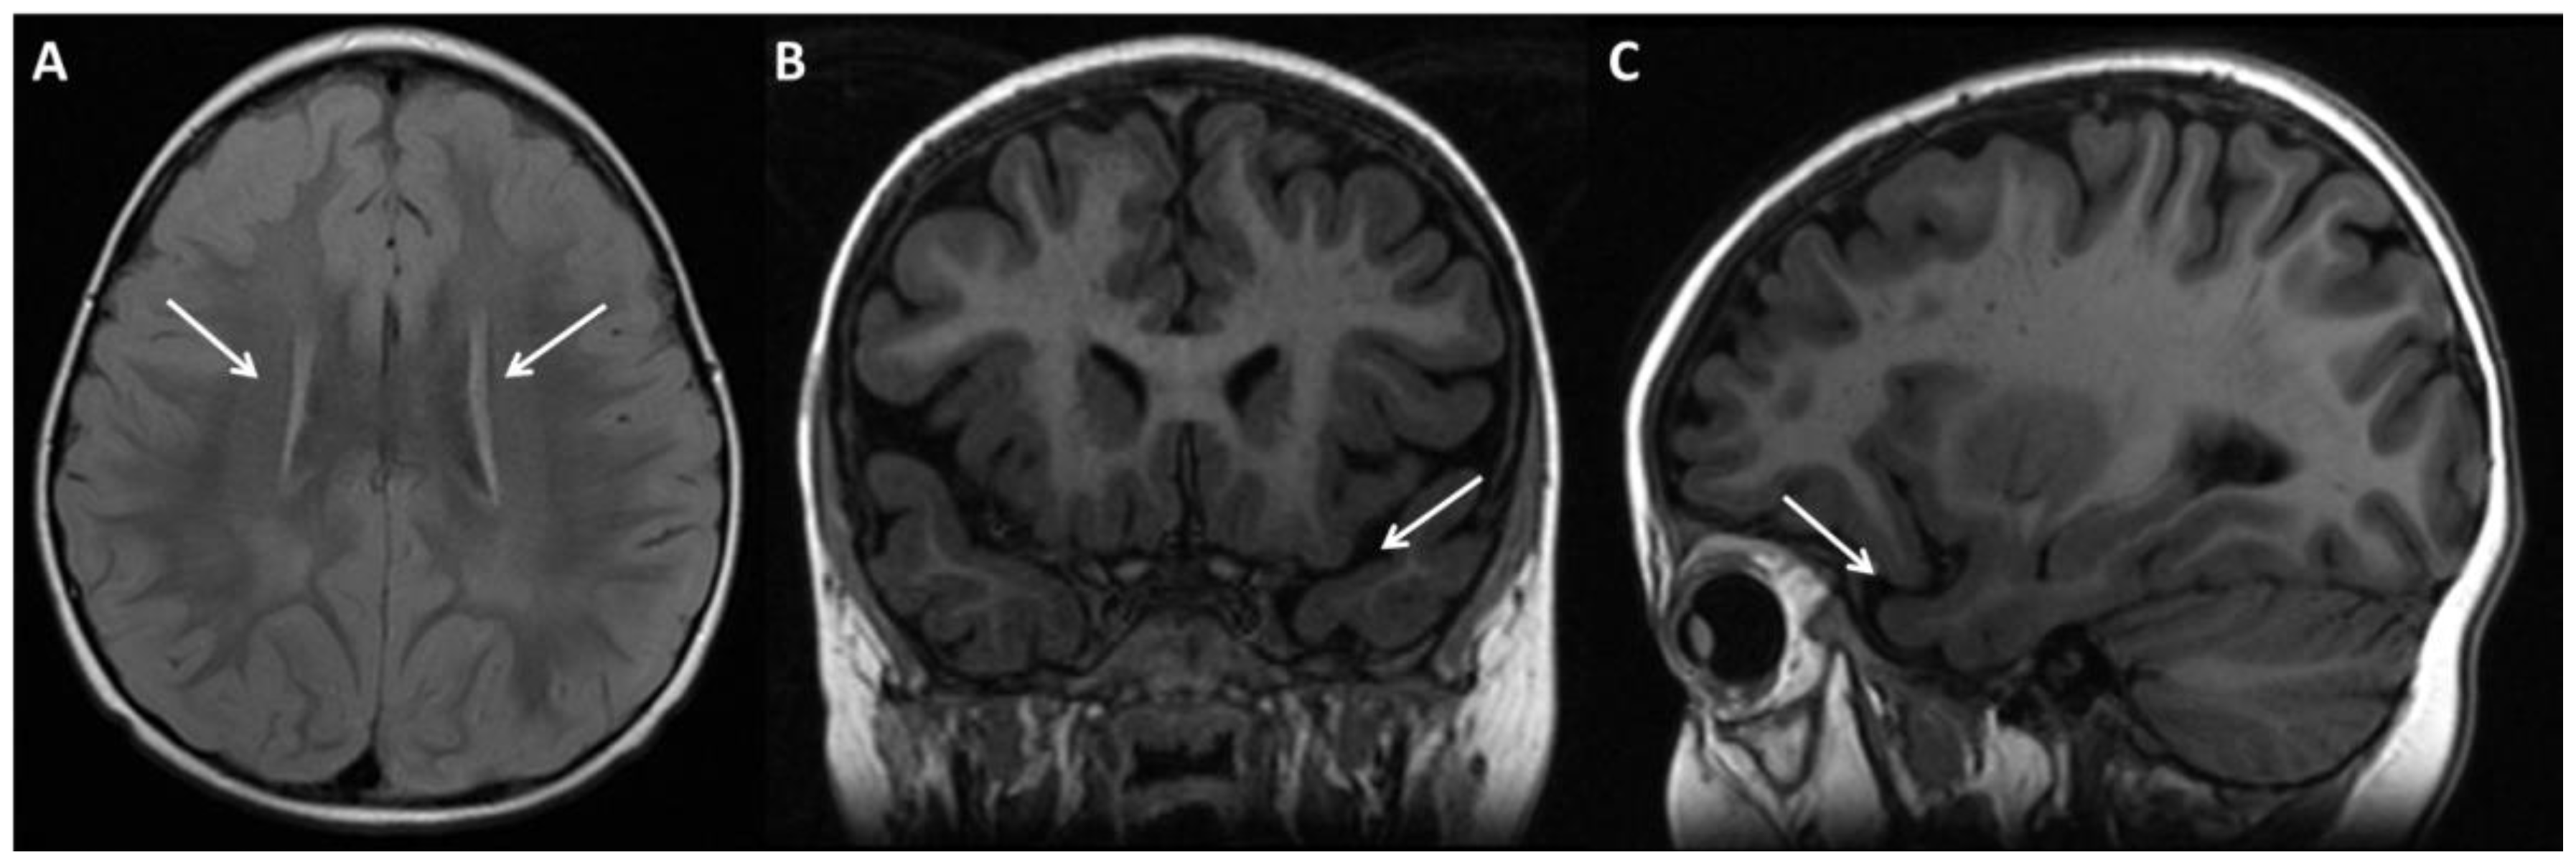

| Brain anomalies (MRI brain) (HP: 0410263) | 3/13 | 23.1 | 2/5 | 40 | 0/0 | 0 | 0/3 | 0 | 5/21 | 23.8 | + | 6/22 | 27.3 | |